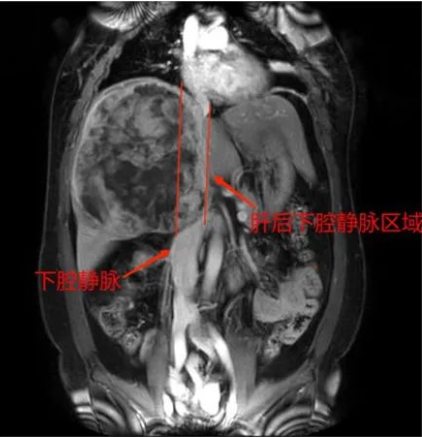

据悉,患者李女士,58岁,因“右上腹部疼痛20天”在当地医院就诊,经检查发现“肝脏巨块型肿物”转入该院。于2022年7月19日收住该院肝胆外科,入院后结合体格检查、血清学检查、腹部MRI检查,诊断肝右叶巨块型肝癌。

由于该肿瘤巨大,占据肝脏的一半,不仅对患者的肝功能造成影响,还会在短期内夺走其生命。针对此情况,红河州第三人民医院专病MDT团队认真组织讨论,制定详细周密的治疗方案。根据该患者肝功能分级评估为A级,尚无远处转移,仔细评估病情后,初步判断病人具备根治性切除术条件,但手术风险仍然较大,经与病人及家属耐心细致的沟通后,其同意接受手术治疗。

经过精心准备、多方论证后,为患者行扩大右半肝切除术。在徐耀端团队、麻醉科、手术室医护人员的密切配合下,历时6个小时顺利完成手术,圆满完整切除了包括瘤体在内的扩大右半肝,切除标本体积约30cm×20cm×15cm,重约4kg。